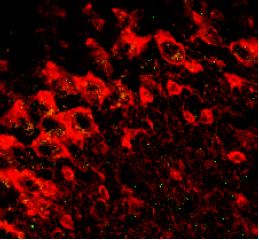

Contributed by W. Hartig and J. Grosche, Leipzig University.